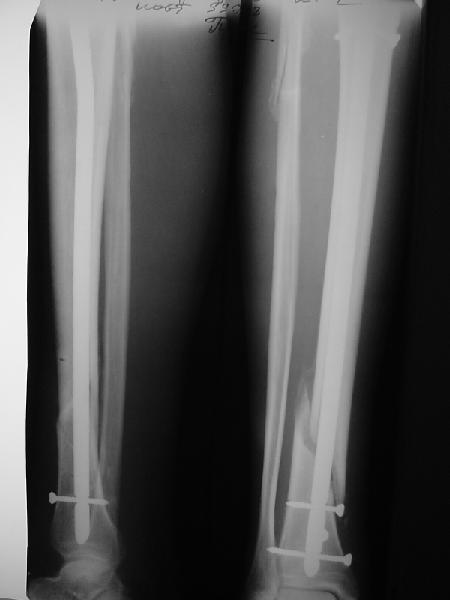

На мой взгляд, на снимках, приведённых Вами - неправильно сростающийся перелом дистальной трети большеберцовой кости, состояние после остеосинтеза интрамедуллярным гвоздём.

Как Вы пишите снимок под номером 1 - менсяц после операции, под номером 2- два месяца после операции.

Вы не послали послеоперационный снимок, поэтому трудно судить о состоянии редукции после операции.

Установка с медиальной стороны гвоздя в области дистального фрагмента дополнительного шурупа помогло бы Вам репонировать и удержать перелом в анатомическом положении, предотвратило варусную деформацию и смещение по ширине.

Пример, приведённый Вами в нашей дискуссии по времени нагрузки после остеосинтеза не совсем удачный... Ваш больной имеет счастье, что первым согнулся проксимальный замыкающий винт, а не дистальный и гвоздь не пенетрировал голеностопный сустав.

Ok. А также и следующий, в 3 месяца.

Как я уже говорил, мы сделали выводы из этого и других подобных случаев. Очевидно, решений проблемы два - либо уменьшить нагрузку, либо увеличить прочность фиксатора. Первое решение работает не со всеми больными, так что пошли по второму пути - мы больше не используем гвозди с запирающими винтами диаметром 4 мм.